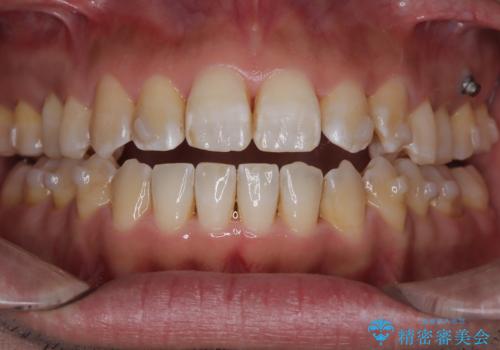

目立たない矯正で八重歯を改善

- 左上の八重歯を気にされて来院されました。精密な検査の結果、歯列全体を広げながら八重歯を奥へ移動させることで、美しい歯並びと機能的な咬み合わせが得られると診断。患者様のご希望に合わせ、透明で目立ちにくい**インビザライン(マウスピース矯正)**による治療計画を立案しました。抜歯を避け、歯を少しずつ遠心(奥)へ移動させることで、歯が並ぶスペースを確保し、叢生(歯のデコボコ)を改善します。

今回の矯正治療では、透明なマウスピース型の装置インビザラインを使用しました。この装置は目立ちにくく、取り外しが可能なため、食事や歯磨きも普段通りに行えます。遠心移動という方法で奥歯を後方に動かし、前歯を並べるためのスペースを確保。これにより、抜歯することなく、左上の八重歯を含む叢生を効果的に改善し、整った美しい歯並びと良好な咬み合わせを獲得していただけました。